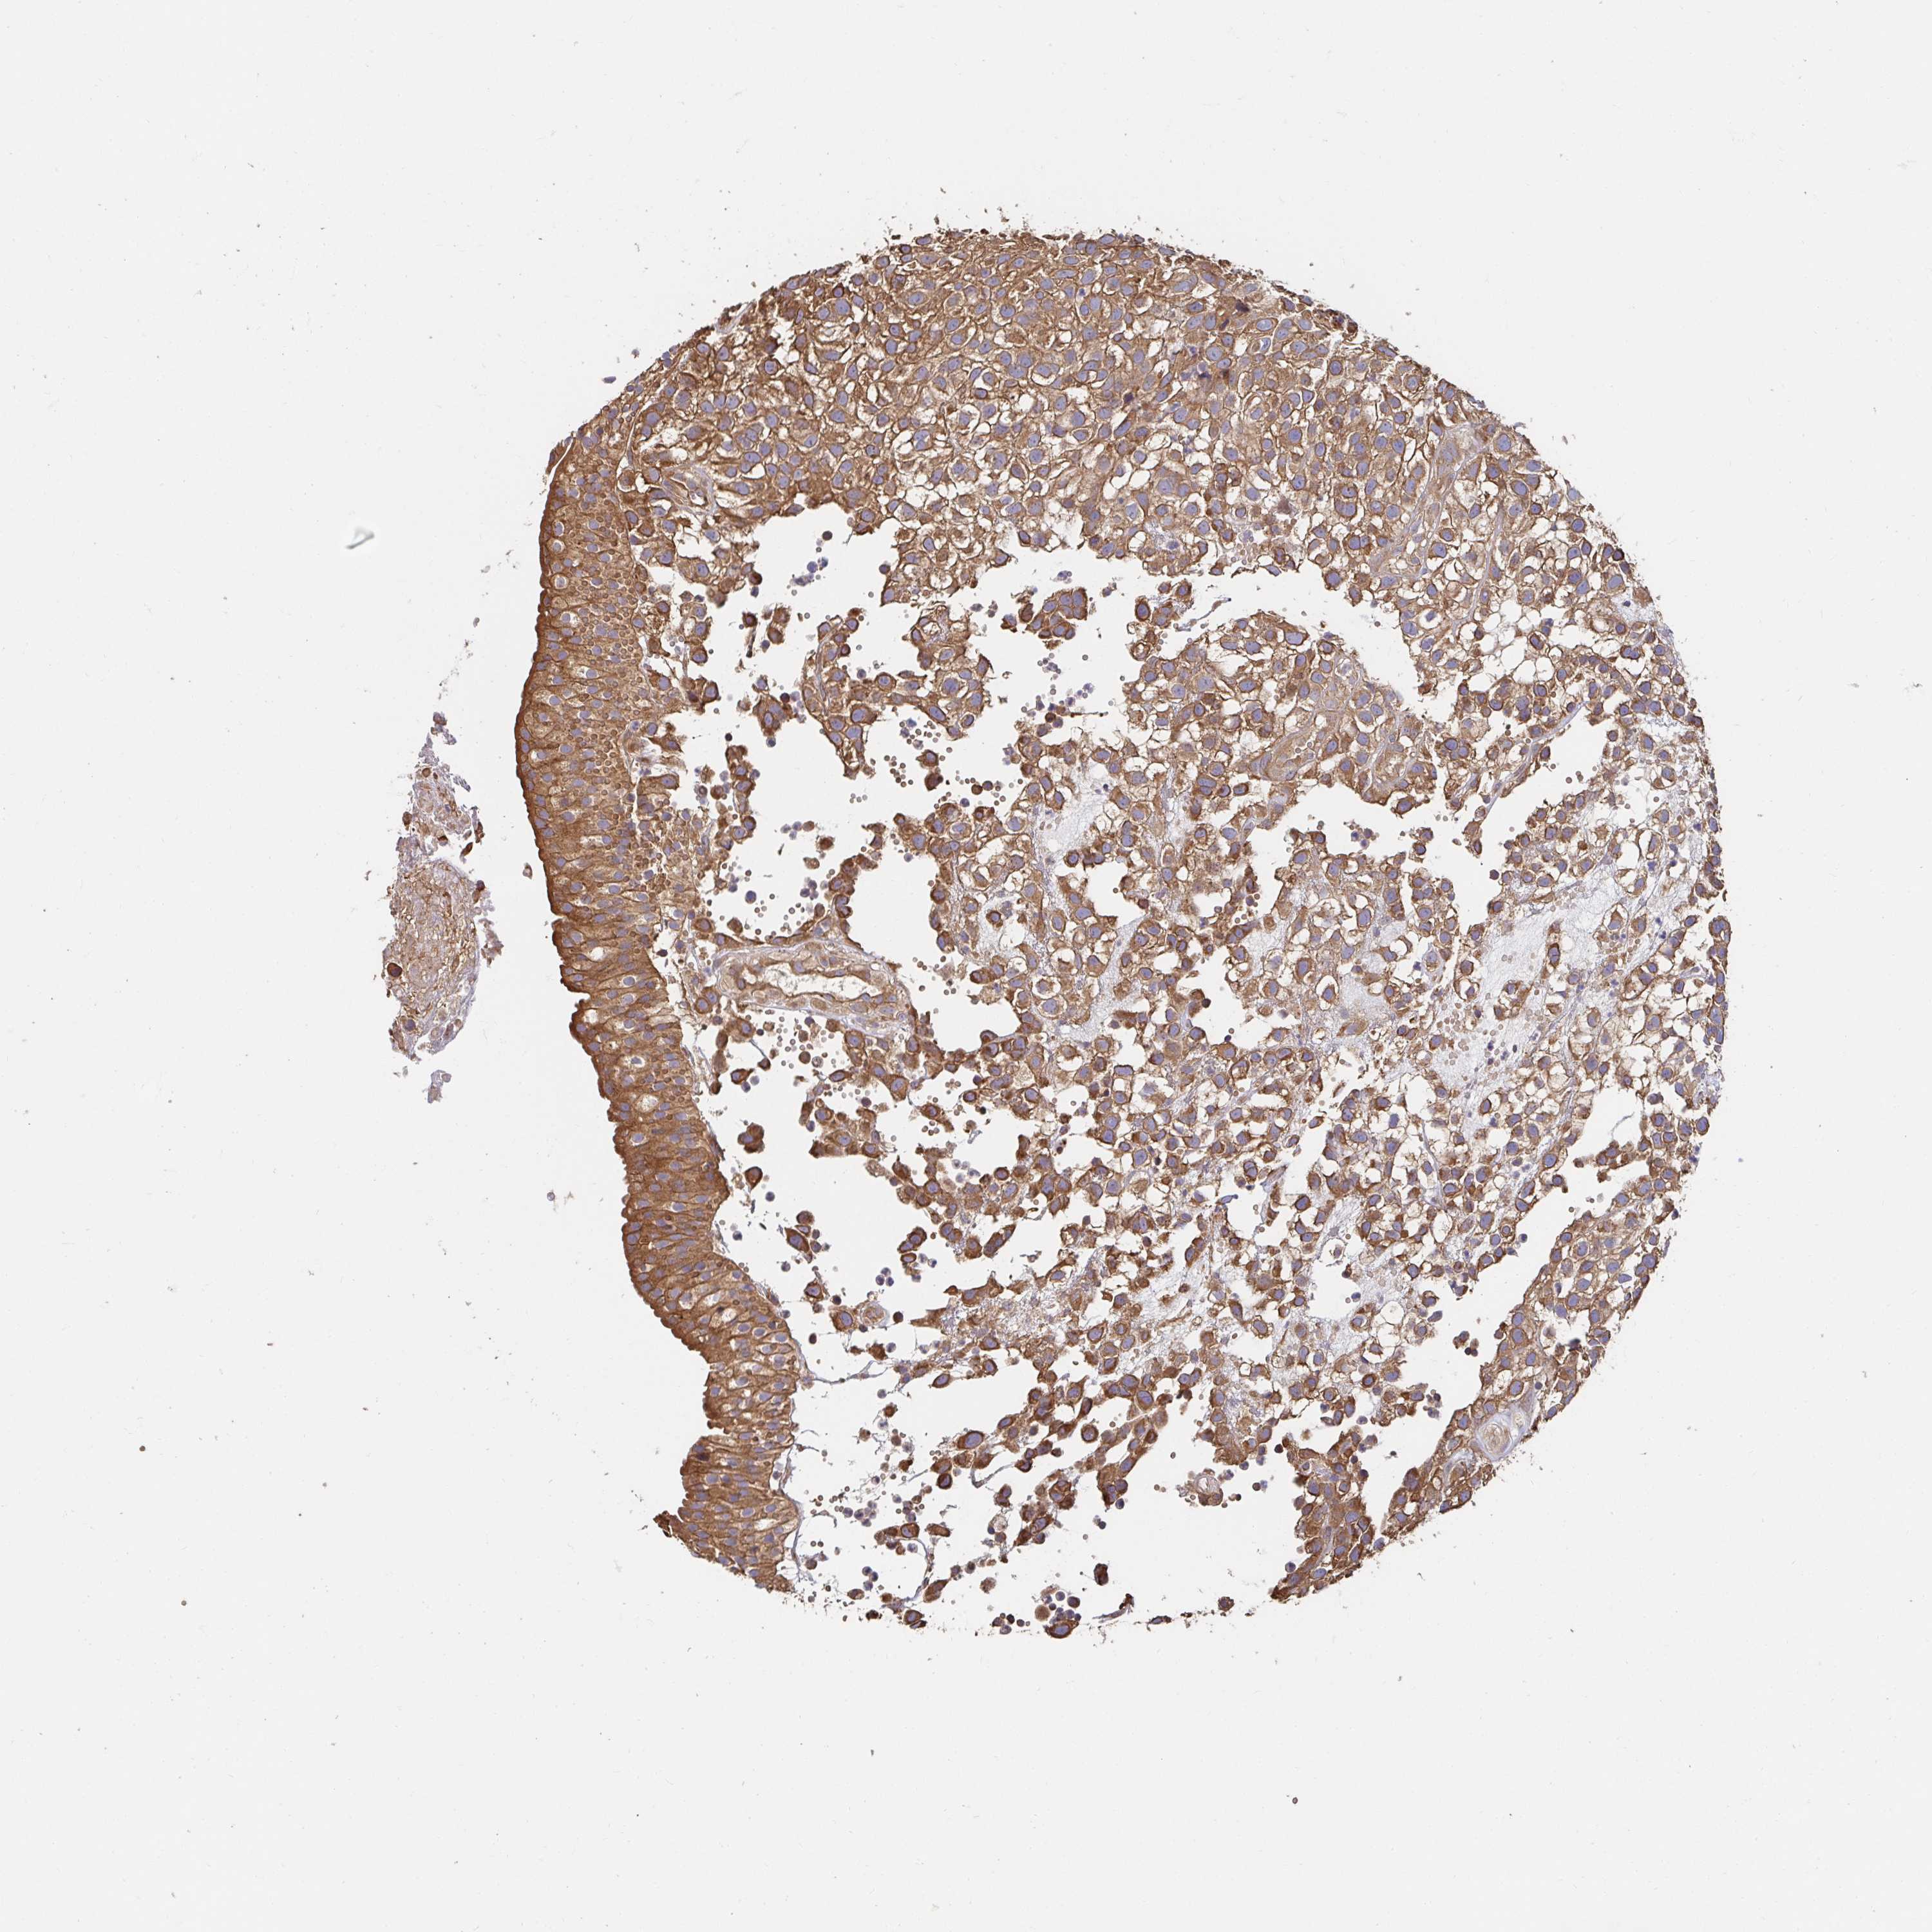

UROTHELIAL CANCER - Protein expressioni

A mouse-over function shows sample information and annotation data. Click on an image to view it in a full screen mode. Samples can be filtered based on level of antibody staining by selecting one or several of the following categories: high, medium, low and not detected. The assay and annotation is described here.

Note that samples used for immunohistochemistry by the Human Protein Atlas do not correspond to samples in the TCGA dataset.

Antibody stainingi

Antibody staining in the annotated cell types in the current human tissue is reported as not detected, low, medium, or high, based on conventional immunohistochemistry profiling in selected tissues. This score is based on the combination of the staining intensity and fraction of stained cells.

Each image is clickable and will lead to virtual microscopy that enables deeper exploration of all samples and also displays staining intensity scores, fraction scores and subcellular localization as well as patient and tissue information for each sample.

Antibody HPA038521

Antibody HPA038522

Staining

High

Medium

Low

Not detected

Intensity

Strong

Moderate

Weak

Negative

Quantity

>75%

75%-25%

<25%

None

Location

Nuclear

Cytoplasmic/membranous

Cytoplasmic/membranous,nuclear

Urothelial carcinoma, High grade

Urothelial carcinoma, Low grade

Urothelial carcinoma, NOS